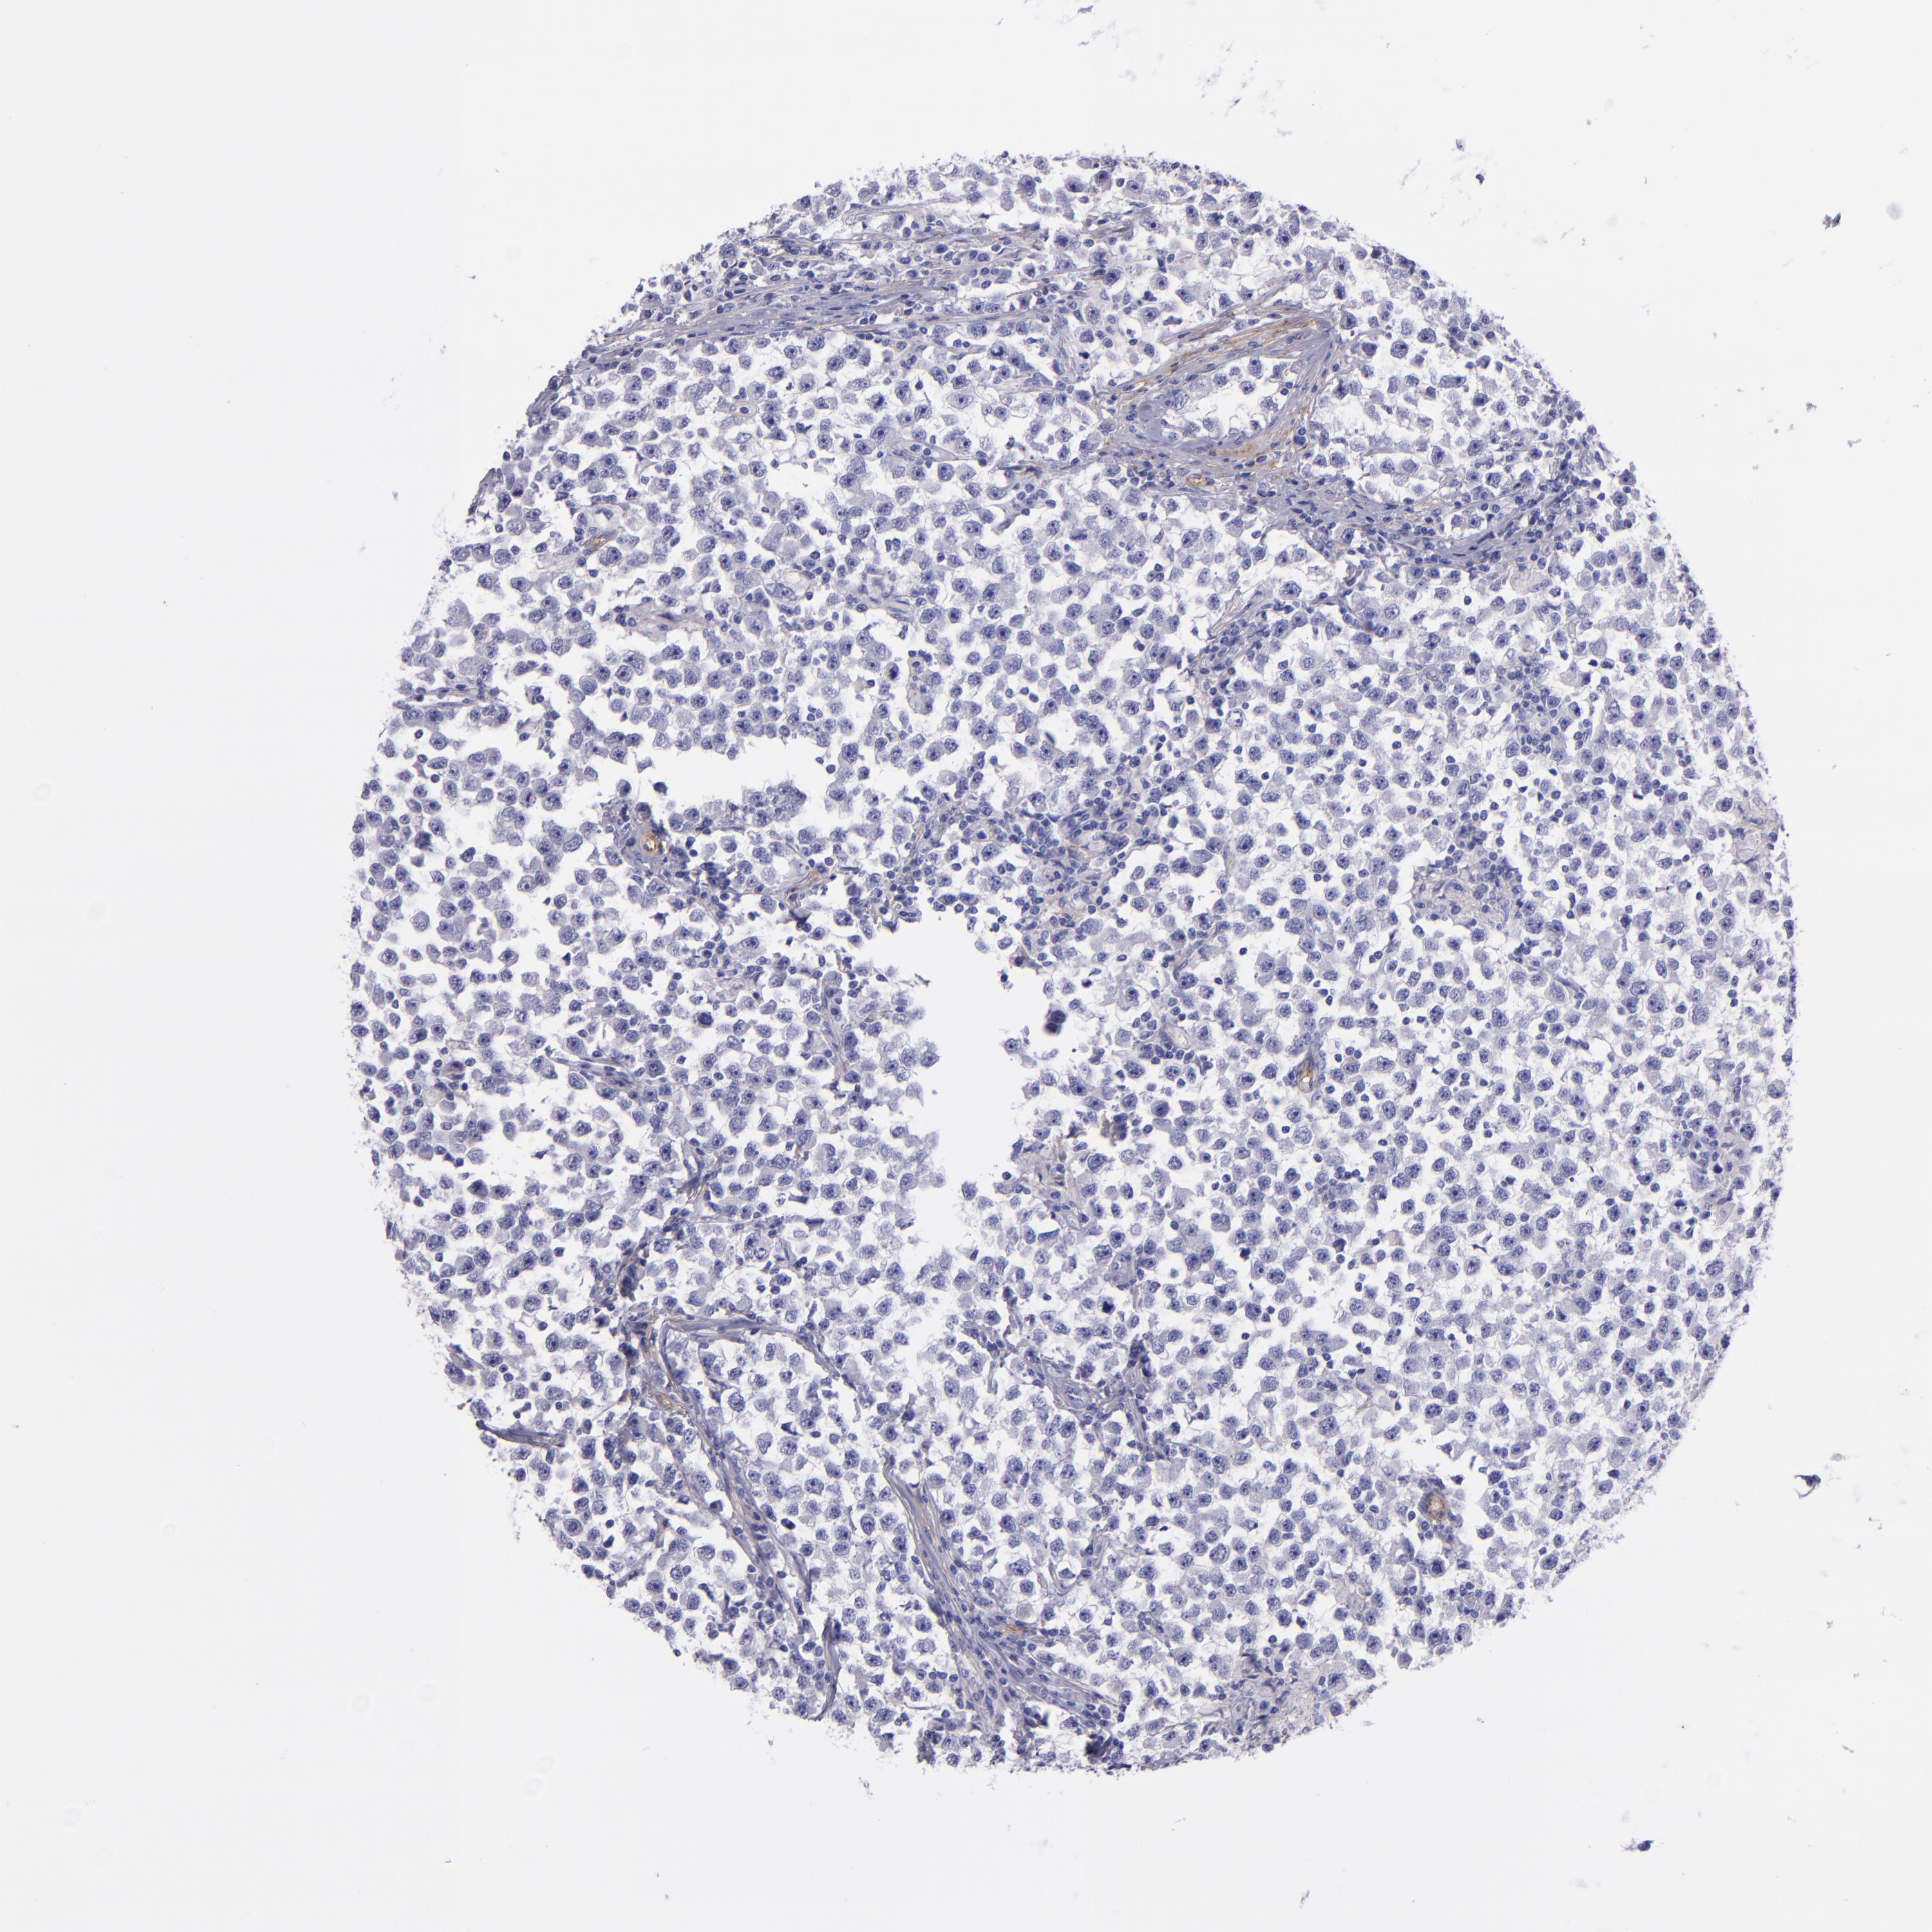

TESTIS CANCER - Protein expressioni

A mouse-over function shows sample information and annotation data. Click on an image to view it in a full screen mode. Samples can be filtered based on level of antibody staining by selecting one or several of the following categories: high, medium, low and not detected. The assay and annotation is described here.

Note that samples used for immunohistochemistry by the Human Protein Atlas do not correspond to samples in the TCGA dataset.

Antibody stainingi

Antibody staining in the annotated cell types in the current human tissue is reported as not detected, low, medium, or high, based on conventional immunohistochemistry profiling in selected tissues. This score is based on the combination of the staining intensity and fraction of stained cells.

Each image is clickable and will lead to virtual microscopy that enables deeper exploration of all samples and also displays staining intensity scores, fraction scores and subcellular localization as well as patient and tissue information for each sample.

Antibody HPA004856

Seminoma, NOS